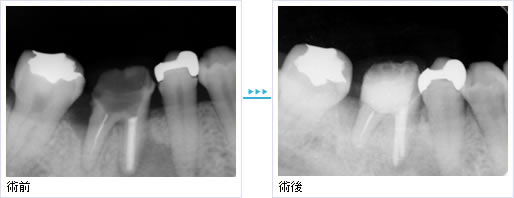

- 骨の再生

- 右下の奥歯が歯周病で骨が減っています。

エムドゲインと人工骨を用いることで、骨の再生が可能となります。